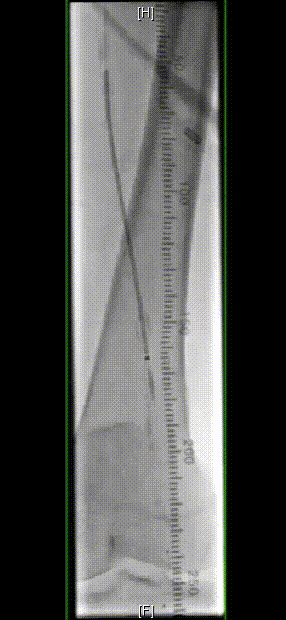

图为:术中造影评估 髂股段

图为:导丝通过病变 置入保护伞 使用Turbohawk定向旋切

图为:股总动脉珊瑚礁病变定向旋切结果股浅动脉段尚未完成定向旋切